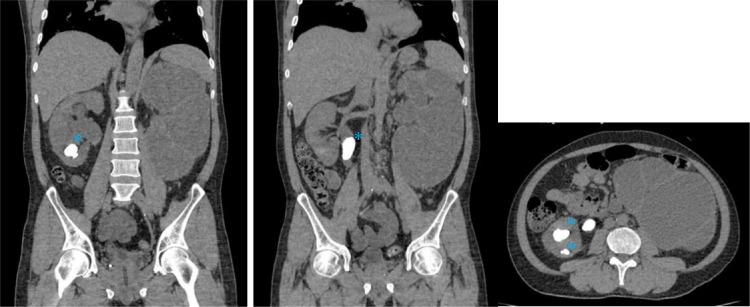

Pyonephrosis is hydronephrosis accompanied by a bacterial infection in the kidney, causing suppurative destruction of the renal parenchyma; this condition is an emergency and usually associated with stones or chronic urinary tract infections. Urinalysis is typically inaccurate for establishing the diagnosis, as bacteriuria may not manifest due to ureteral obstruction. We reported a 55-year-old male patient with flanks pain and an account of stone expulsion. Based on history taking, physical examination, radiology examinations, and percutaneous nephrotomy, we concluded a diagnosis of pyonephrosis causing by as known as Group B Streptococcus. While both US and CT scan guided the early diagnosis, CT was more accurate as it is able to capture the renal function and the underlying cause of obstruction. Pyonephrosis was described as having a pus collection in the pelvicalyceal system, cortex thinning, and the appearance of stones. Pyonephrosis is a rare emergency, and many clinicians find it challenging to recognize since the presentations are frequently nonspecific. In order to prevent renal failure and the spread of bacteremia that entails life-threatening urosepsis, acquiring imaging knowledge (sonography and CT) and other findings are indispensable in determining this entity.